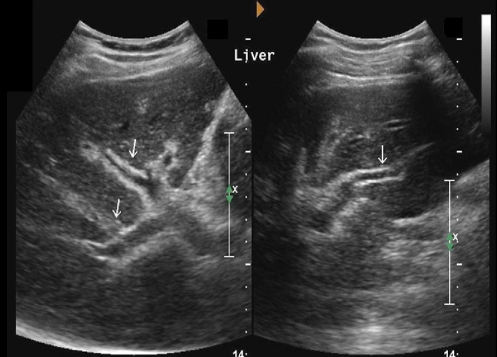

Identify this image.

Schistosomiasis